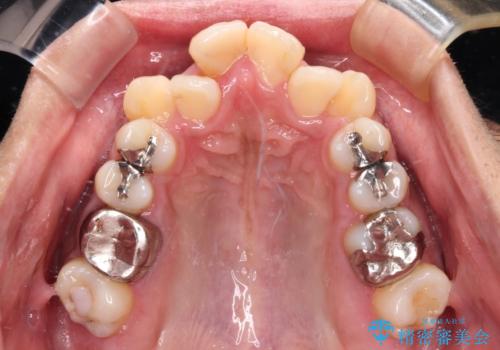

八重歯と開咬 ワイヤー装置での抜歯矯正

- 前歯のデコボコと八重歯、開咬を気にして来院された患者様です。

骨格的に下顎骨が上顎骨に対して後退位であったため、上顎の左右第一小臼歯を抜歯し、デコボコを改善するとともに開咬を改善していくこととしました。

自己管理が煩わしいとのことで、表側のワイヤー装置にて治療を進めて行くこととしました。